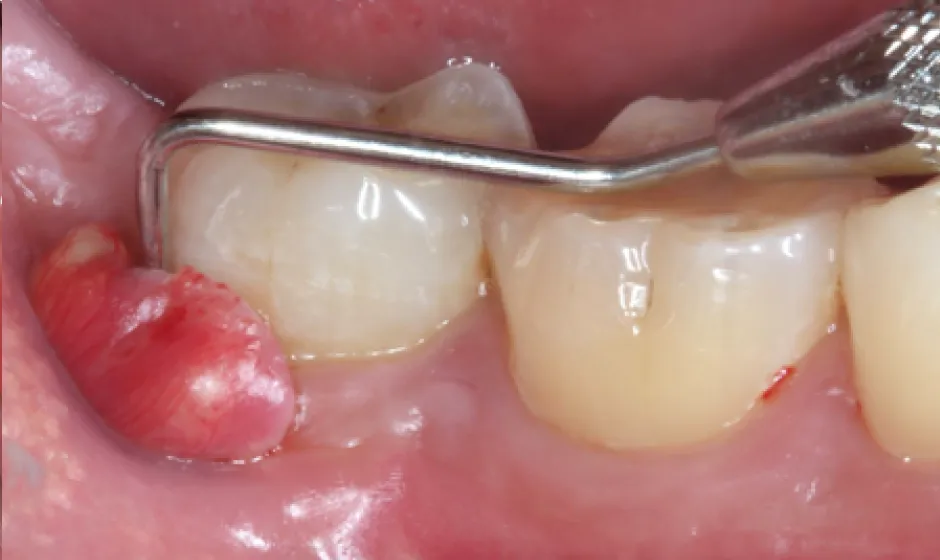

02歯周病・

重度歯周病治療歯周病は痛みが少ないまま進行し、気づいた時には歯がグラつく、膿が出る、噛みにくいといった状態になりやすい病気です。けれど、重度でも「もう無理」と決めつける前に、歯ぐき・骨・噛み合わせの状態を丁寧に評価し、今できることを一つずつ積み上げれば、守れる歯はあります。

当院では検査に基づき、基本治療から必要に応じた外科的治療や再生療法の検討まで、長期維持を見据えて段階的に進めます。津市で歯周病を本気で治したい方に、寄り添える歯科医院でありたいと考えています。症例1

症例2

- 治療名

- 【高度審美形成】歯間乳頭再建術

- 患者様

- 40代女性

- 執刀医

- Dr. 大杉

- 治療期間

- 約1年

- 治療費

- 300,000円(税込)

- リスク

- 移植組織の定着後も、メンテナンスが予後を大きく左右します。

特に歯間ブラシの不適切な使用や過度なブラッシング圧は組織の退縮を招くため、術後は当院の指導に基づいた厳密なプラークコントロールが必要です。